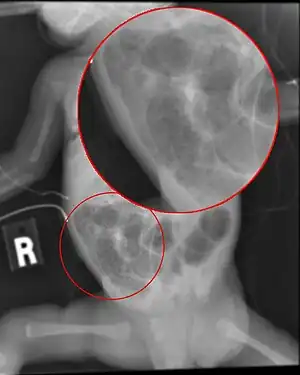

The diagnosis is usually suspected clinically but often requires the aid of diagnostic imaging modalities, most commonly radiography. Specific radiographic signs of NEC are associated with specific Bell's stages of the disease:[6]

- Bell's stage 2 (definite disease):

- Mild to moderate systemic signs

- Additional intestinal signs (absent bowel sounds, abdominal tenderness)

- Specific radiologic signs (pneumatosis intestinalis or portal venous gas

- Laboratory changes (metabolic acidosis, too few platelets in the bloodstream)

- Bell's stage 3 (advanced disease):

- Severe systemic illness (low blood pressure)

- Additional intestinal signs (striking abdominal distention, peritonitis)

- Severe radiologic signs (pneumoperitoneum)

- Additional laboratory changes (metabolic and respiratory acidosis, disseminated intravascular coagulation)